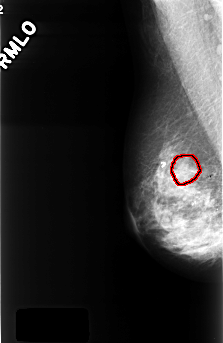

C_0394_1.RIGHT_MLO

RIGHT_MLO LINES 4448 PIXELS_PER_LINE 2896 BITS_PER_PIXEL 12 RESOLUTION 50 OVERLAY

FILE: C_0394_1.RIGHT_MLO.OVERLAY

TOTAL_ABNORMALITIES 1

ABNORMALITY 1

LESION_TYPE CALCIFICATION TYPE AMORPHOUS DISTRIBUTION CLUSTERED

ASSESSMENT 4

SUBTLETY 2

PATHOLOGY BENIGN

TOTAL_OUTLINES 1

BOUNDARY